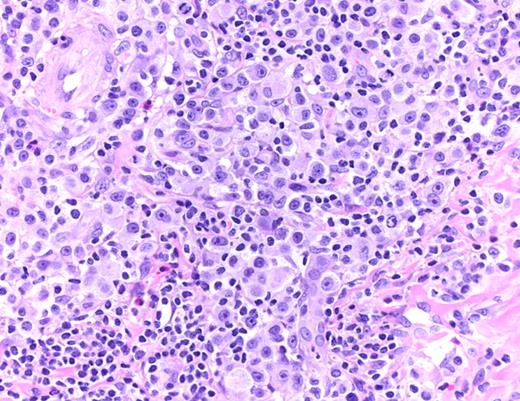

The histologic features of LYP are variable and depend on the evolution of the lesions. Four histologic subtypes (A-D) have been delineated, which represent a spectrum with overlapping features and may be present in individual patients at the same time15,16 (Table 1). Immunohistochemistry plays a pivotal role by revealing the presence of CD30+ large pleomorphic or anaplastic T cells. By definition, CD30 is expressed by at least 75% of the tumor cells in PCALCL.1-3 Differentiation of LYP and PCALCL from other forms of CTCL and secondary cutaneous involvement by nodal Hodgkin lymphoma or systemic ALCL requires careful clinicopathologic correlation.17,18

LYP: Large pleomorphic and anaplastic tumor cells intermingled with small lymphocytes, eosinophils, and histiocytes (hematoxylin and eosin, original magnification ×200). Histologic photomicrograph was captured using a digital camera (AxioCam MRc5; Zeiss) mounted on an Olympus microscope (BX45; Olympus). Objective lens: 400×/0.75 NA. Imaging software: Axio Vision Release 4.8.2 (Zeiss) and Adobe Photoshop Version 8.0 (Adobe Systems).